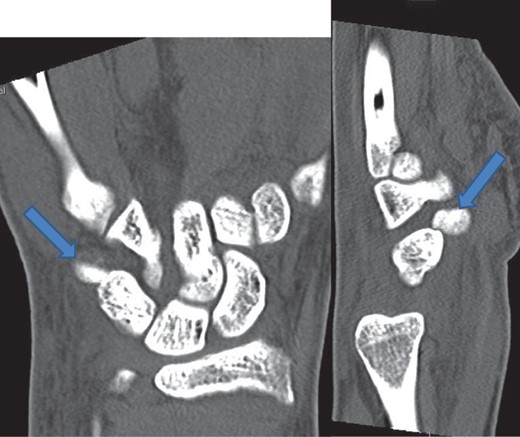

The X-rays of the patient was later reviewed by the duty radiologist and reported as a suspected dislocation of the pisiform bone, Fig. 1. Therefore the patient was recalled to the trauma clinic after three days. He was reassessed and a further three dimensional scan of the wrist was arranged. The CT scan demonstrated distal dislocation of the pisiform which appeared to lie in a ‘locked’ position beyond the distal triquetrum, Fig. 2.

CT showing pisiform displaced from its anatomical position confirming dislocation.